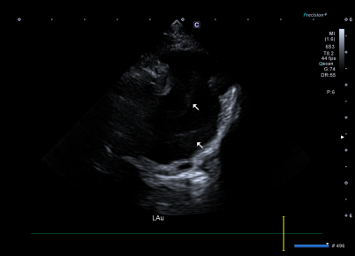

- 좌심방 및 좌심방이 내부에서 Spontaneous Echo Contrast(SEC) 가 관찰되었는데, 이는 혈액 흐름이 느려지면서 혈전이 생기기 쉬운 상태임을 의미합니다.

환자의 심장초음파 사진(좌심이 내 spontaneous echo contrast (SEC) +) / 출처: 24시 동탄리더스동물의료원